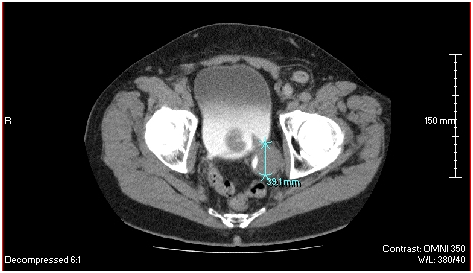

The patient is a 63 year-old male diagnosed in February 2010 with transitional cell bladder carcinoma located at the left posterior ureterovesical junction. The initial CT scan showed the tumor measured 3.91 cm in its posterior to anterior diameter (Figure 2). A plant-derived extract called Salicinium, which is thought to be selectively toxic for cancer cells, was prescribed by his physician. By 3 months, however, the tumor had grown to approximately 7 cm x 4 cm, with compression of the bladder wall (Figure 3). The patient’s physician then decided to try intravenous Enercel. The patient gained symptomatic relief and over the next 2 weeks reported passing blood and tissue pieces in his urine. After 12 weeks of Enercel therapy the tumor had decreased back to 4.01 cm in its widest diameter and was no longer compressing the bladder (Figure 4). The volume of the tumor since beginning of the Enercel therapy was estimated to have decreased by 53%. Hypodense areas were seen inside and along the edges of the mass consistent with tumor cell necrosis. Symptomatically, the patient reported feeling much improved in his overall health. Rather than continuing with Enercel, the patient opted to travel to Mexico for stem cells, catheter administration of supplements and attempted catheter removal of residual tumor. These endeavors led to Pseudomonas aeruginosa sepsis that failed to respond to months of antibiotic therapy. Surgery was finally attempted but failed and the patient died. The case is informative, however by the Enercel induced a significant reduction in tumor size (7 cm versus 4 cm largest diameter) and the clinical and radiological evidence of apparent tumor necrosis.

Figure 4 A CT scan of the pelvis of the same patient obtained on 8-12-2010. The radiologically defined tumor had reduced in size and was no longer compressing the bladder. Its widest diameter was 4.01 cm. The volume of the tumor was estimated to have been reduced by 53%. Hypodense areas were noted within the outer margins of the mass and were interpreted as areas of cellular necrosis.